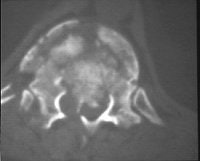

Finally, MRI can be used to study dural tears resulting from spinal fractures. Dural tears may result in entrapment of nerve roots between laminar fragments (images H-J above). Such dural tears may delay, if not preclude, recovery, El-Khoury said. MRI has been found to be 100% sensitive and 74% accurate for diagnosing dural tears as a result of burst fracture, he added.

![]() ![]() ![]() |